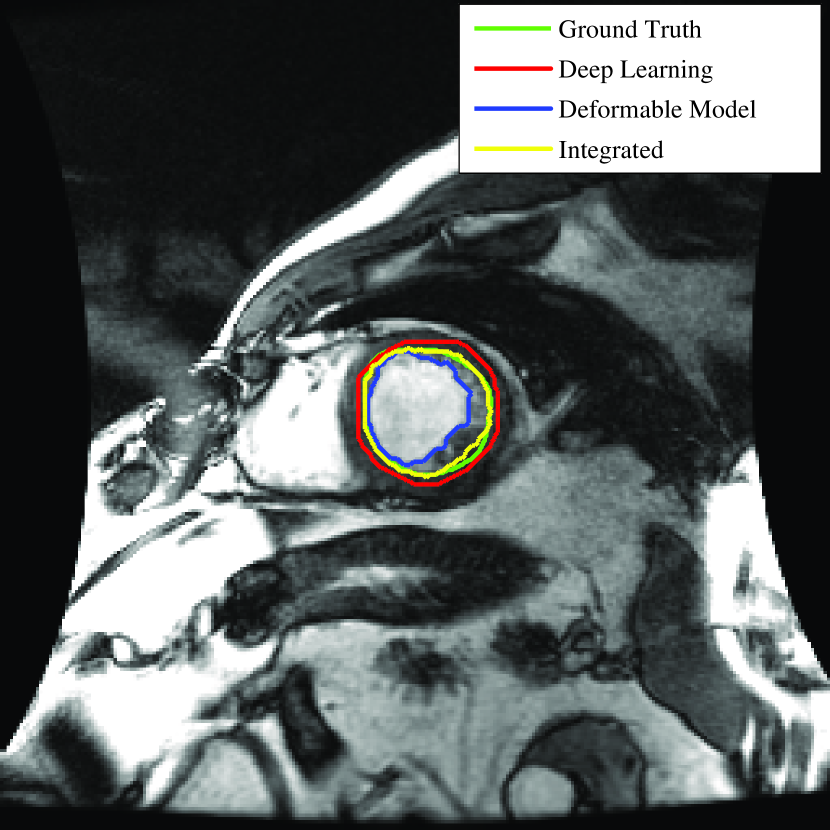

To better understand the role of each step, the outcome of the deformable model with no shape constraint (), deep learning (shape inference, Step 2) and the integrated deformable model and deep learning method (final step) for two typical images are shown in Fig. 8.

As seen in the left side of Fig. 8, the outcome of the deformable model without shape constraint (blue) leaked to surrounding tissues due to low contrast at the borders. Clearly this is not acceptable. On the other hand, the deep learning network (shape inference) provided a close contour (red) to the ground truth (green) with no leakage. This is due to the fact that the network has been trained using the ground truth data to look for the overall shape of the LV and not the intensity difference at the border. Finally, the integrated deep learning and deformable models brought the contour (yellow) closer to the ground truth. Similar behavior can be seen in the right side of Fig. 8 when contours tend to shrink due to presence of papillary muscles in the LV.